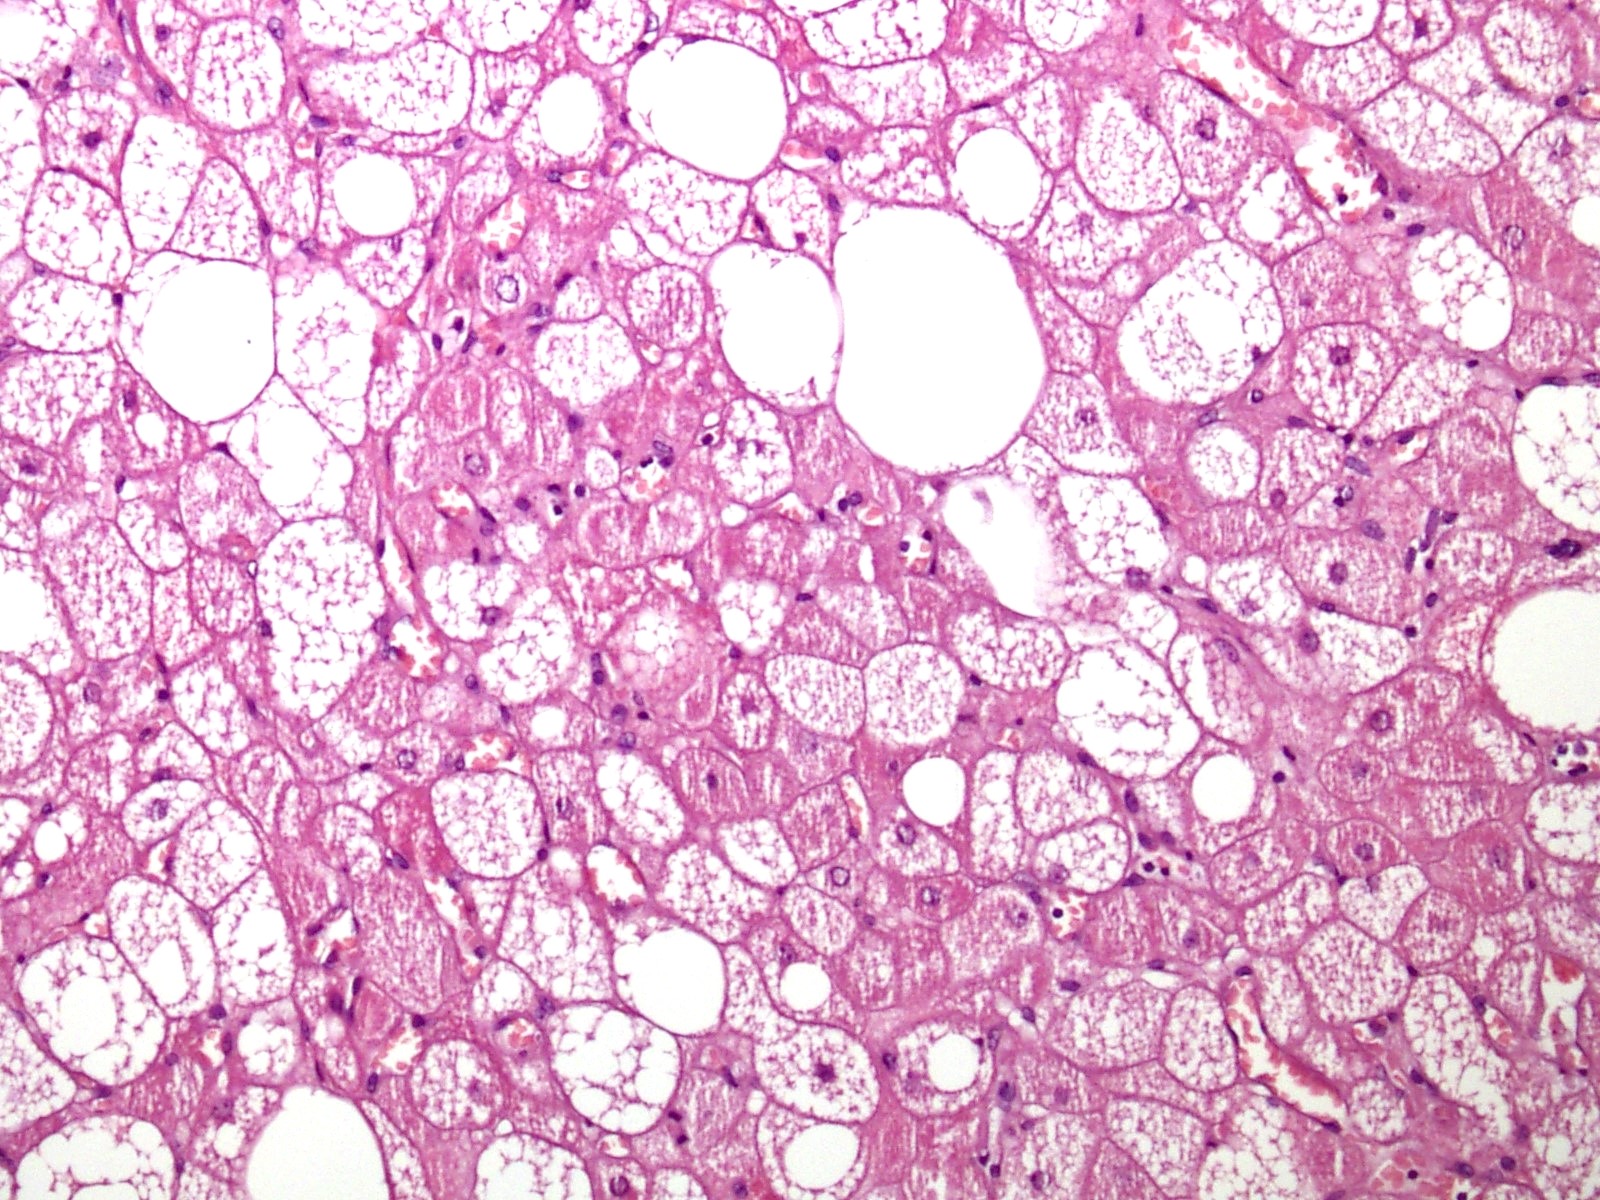

Microscopic (histologic) description

- Neoplastic lesion composed of polygonal brown fat cells with stromal cells in the background (Case Rep Oncol 2017;10:438)

- Large number of pale and eosinophilic brown fat cells with multivacuolated, eosinophilic granular cytoplasm and small central nucleus (about 70%) admixed with variable amount of univacuolated white cells (Case Rep Oncol 2017;10:438, Am J Case Rep 2020;21:e921447, J Comput Assist Tomogr 2019;43:793, J Pathol Transl Med 2017;51:499, Am J Surg Pathol 2018;42:951, Virchows Arch 2021;478:527)

- Multivacuolations resemble lipoblasts

- Morphological variations or subtypes: typical, myxoid (9%), lipoma-like (7%), spindle cell (2%), thick bundles of collagen fibers, presence of mast cells and exclusively containing brown fat cells (Case Rep Oncol 2017;10:438, Am J Case Rep 2020;21:e921447, Virchows Arch 2021;478:527)

- Cytological atypia, necrosis and mitosis is unusual (J Pathol Transl Med 2017;51:499, Am J Surg Pathol 2018;42:951, BMC Surg 2021;21:30)

Microscopic (histologic) images

- Microscopic description: The sections reveal a well circumscribed neoplastic lesion comprising large polygonal cells arranged in sheets. These cells have multivacuolated, granular cytoplasm with small central nucleus admixed with variable amount of univacuolated cells. There is no significant cytological atypia, necrosis or mitosis.